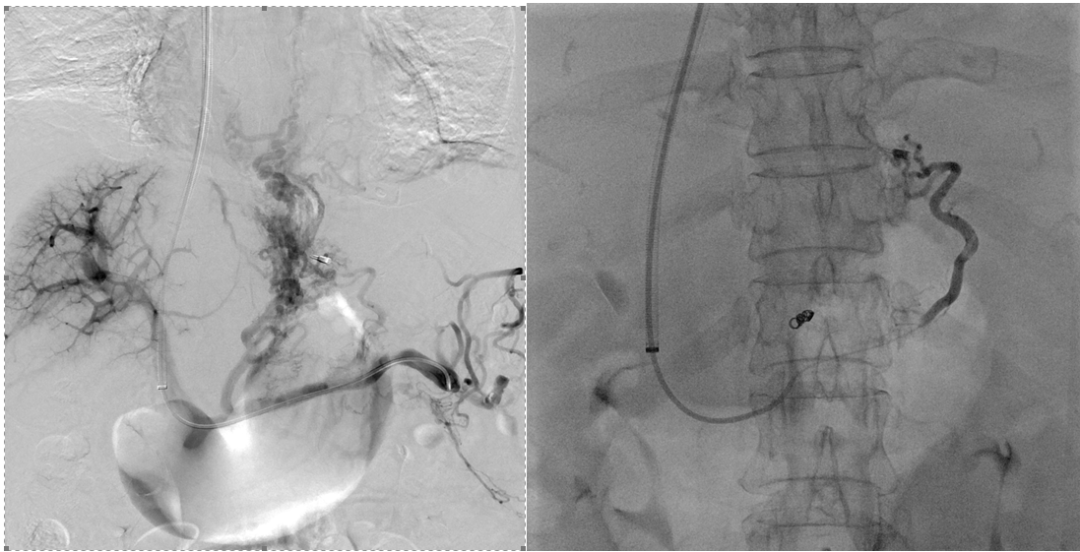

经过仔细分析、反复讨论,介入科团队于10月25日成功为患者实施了TIPS手术,术后患者门静脉压力从32mmHg降低至22mmHg,并对曲张的食管胃底静脉进行了栓塞,大大降低远期再出血风险。术后患者生命体征平稳,相关检验检查结果满意,受到了患者及家属的好评和认可。

经颈静脉肝内门体静脉分流术是介入放射学治疗门静脉高压的有效手段之一。TIPS手术是介入手术中的四级手术,难度大、风险高,被誉为介入手术中的“天花板”。TIPS术通过在肝静脉与门静脉之间的肝实质内建立分流道,降低门静脉压力,同时栓塞迂曲扩张的出血血管,控制和预防食道胃底静脉出血,促进腹水的吸收。

手术简要过程示意图

手术分流术后效果图